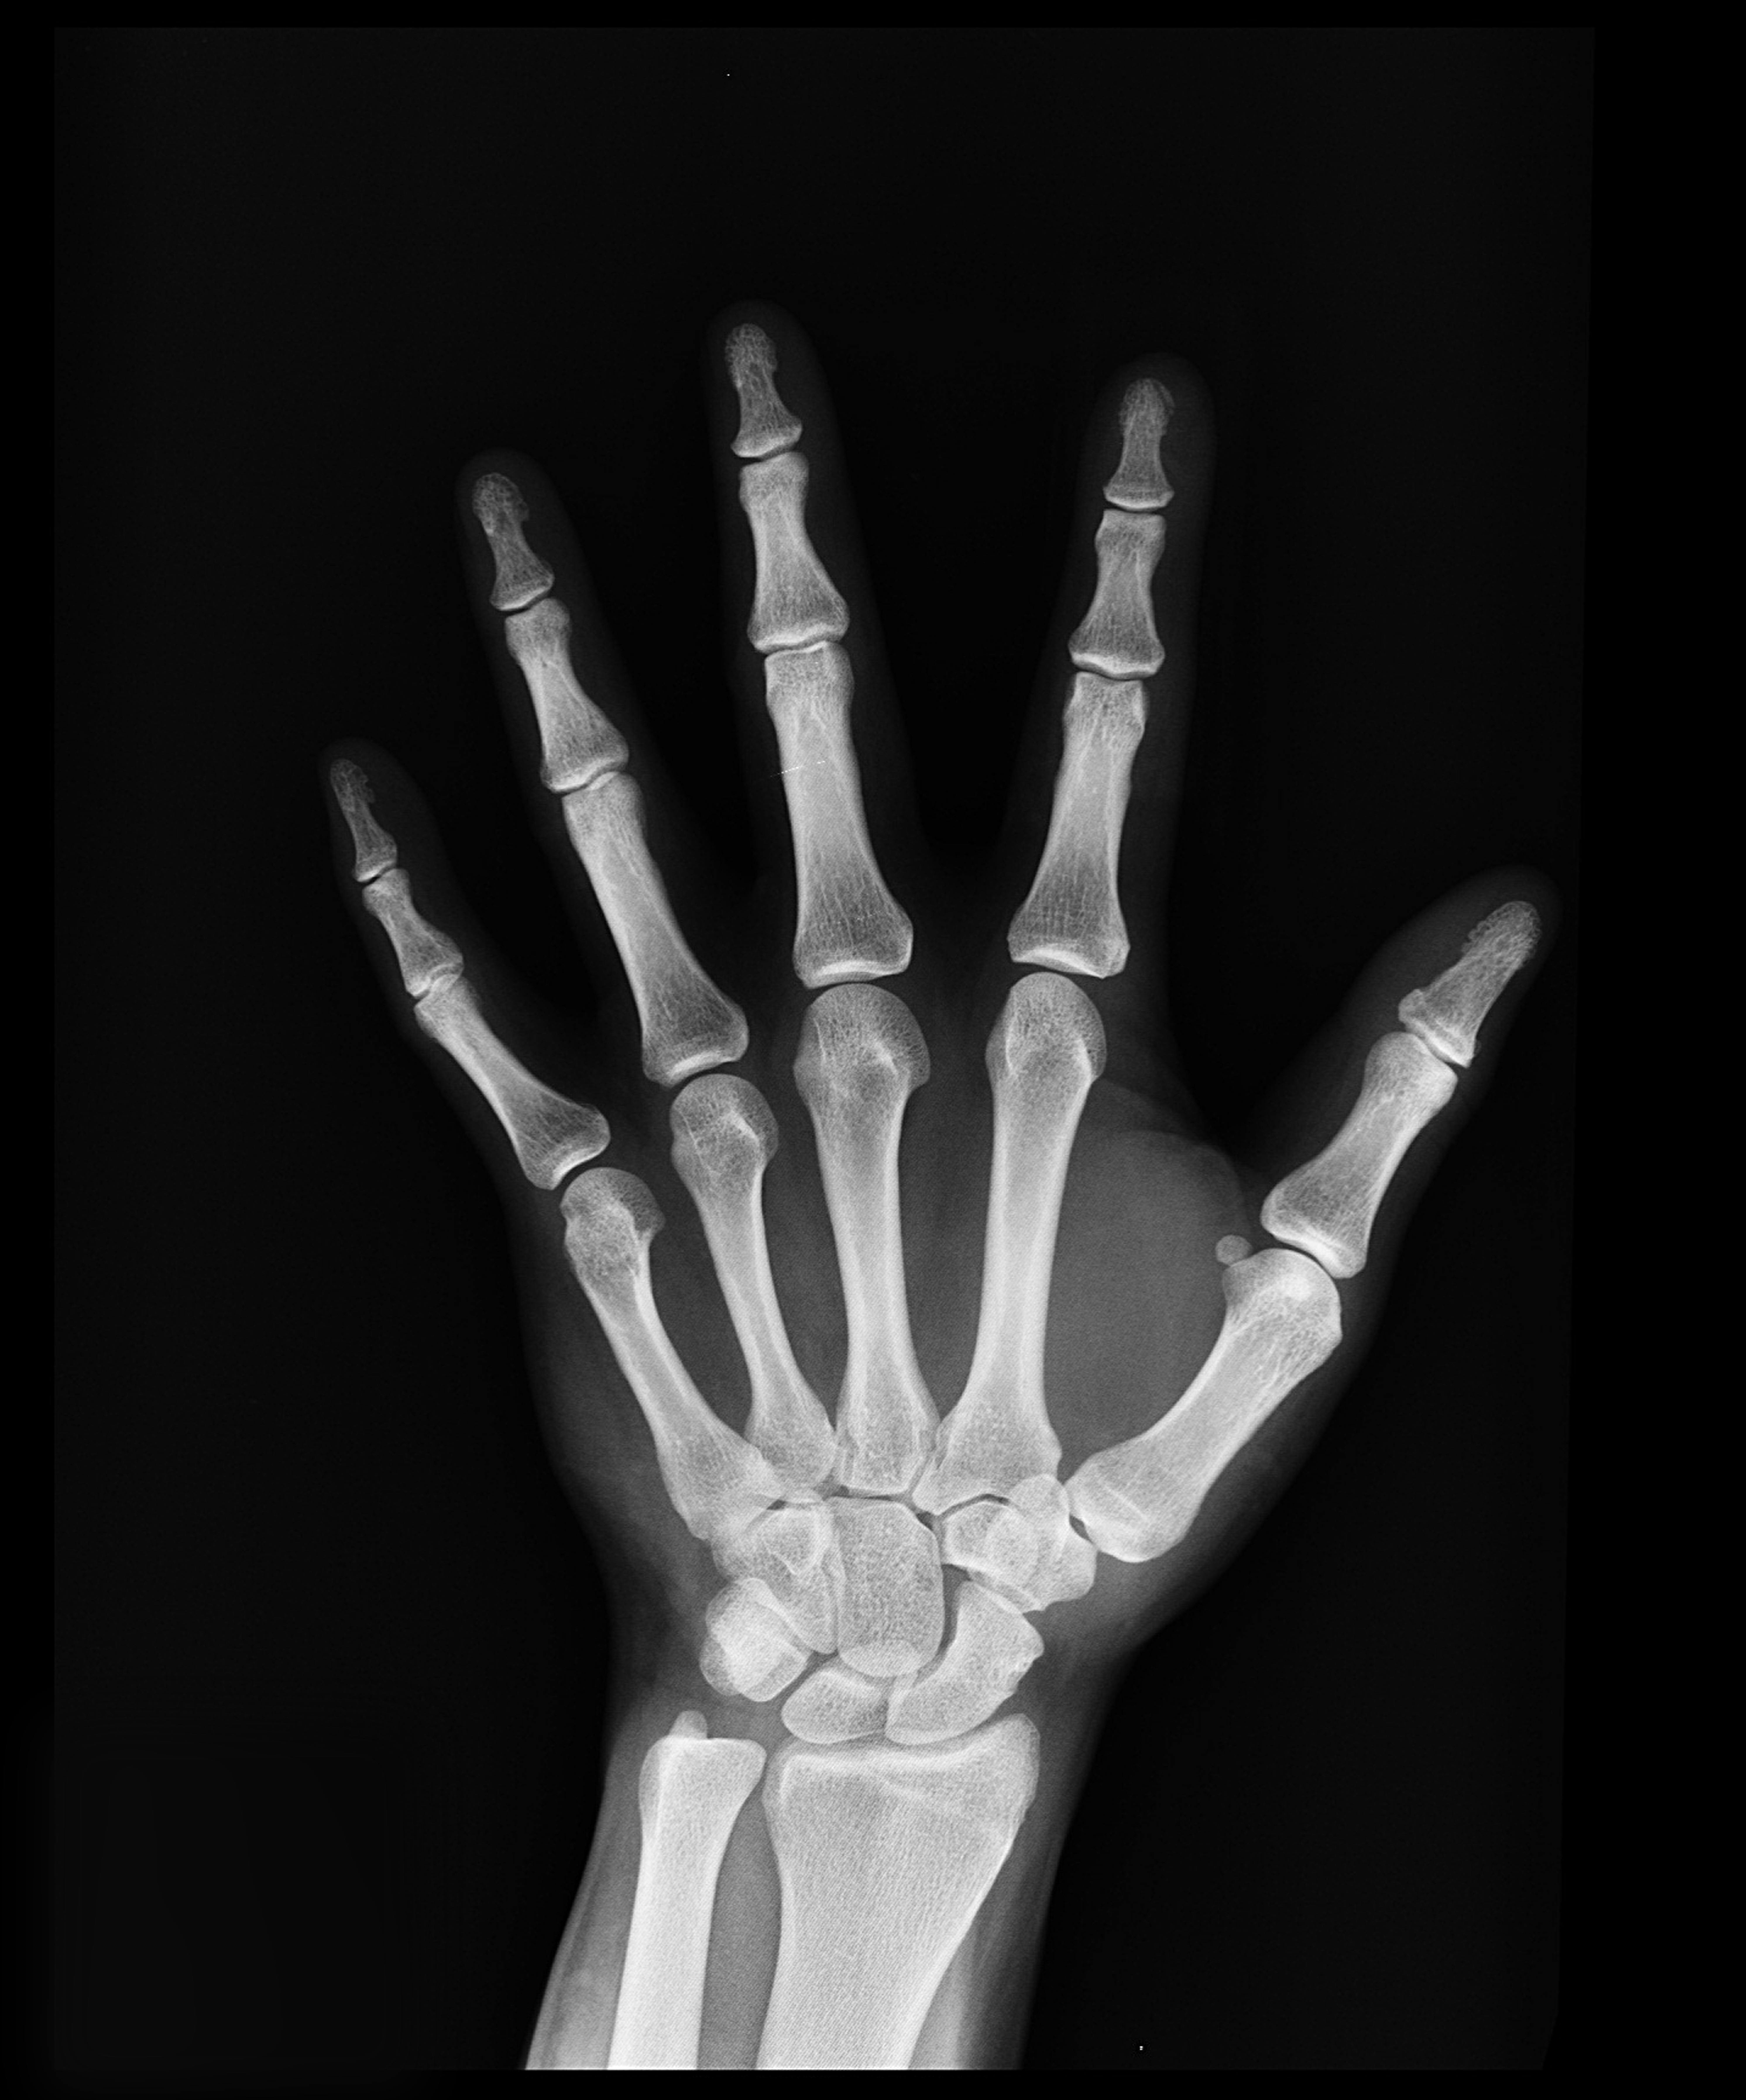

Existen pruebas específicas que miden la Densidad Mineral Ósea (DMO) en diferentes partes del cuerpo cuya función es proporcionar una evaluación instantánea de la salud ósea. Esta prueba detecta la osteoporosis, evalúa el riesgo de fracturas y permite monitorear la respuesta al tratamiento osteoporótico.

Foto de Pixabay: https://www.pexels.com/es-es/foto/resultado-de-la-radiografia-de-la-mano-207496/